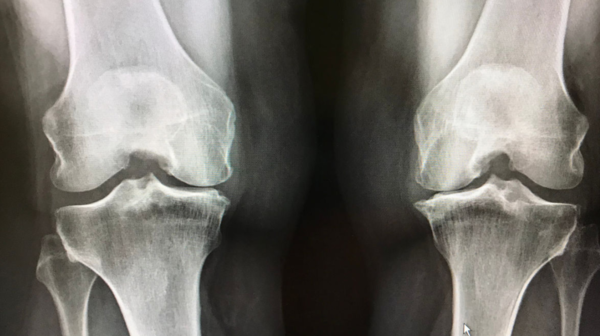

ㅣ데일리포스트=김정은 기자ㅣ직립 2족 보행을 가능하게 하는 무릎은 인간의 특징적 기관 중 하나지만, 나이가 들수록 통증이 늘고 움직임이 어려워지는 부위이기도 하다. 인간의 무릎 진화에는 복잡한 역사가 존재하며 통증을 느끼거나 다치기 쉬운 원인도 그 역사에 있다.

6000년 전까지 살았던 수렵채집민 유골을 분석한 2017년 연구에서 현대에는 45세 이상인 사람의 3분의 1 이상이 겪는 '변형성무릎관절증'이 과거에는 전혀 문제가 되지 않았을 가능성이 높은 것으로 나타났다.

이 연구에 따르면 현대 인간이 직면한 무릎 문제 대부분은 산업화 사회의 앉아서 생활하기 쉬운 라이프스타일로 인해 발생률이 2배 이상 늘어난 것으로 추정된다.